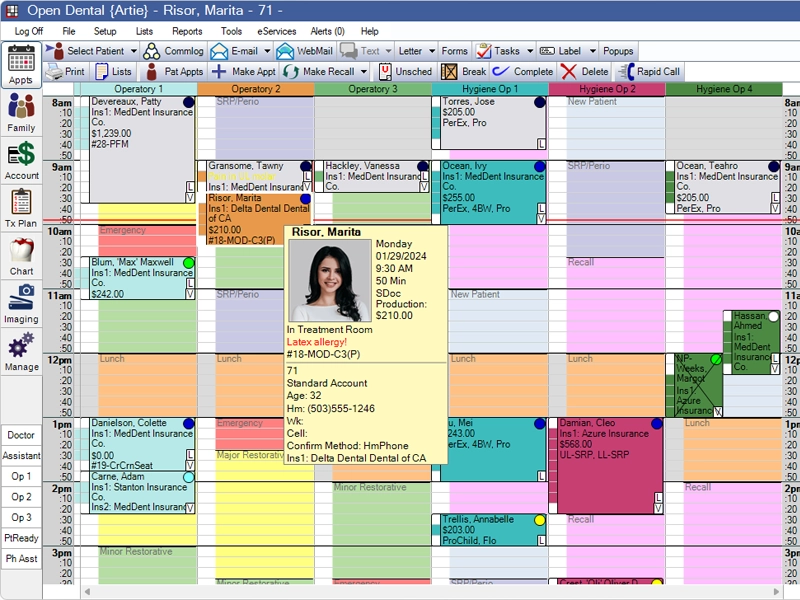

⏱️ Fewer Office Visits

No adjustments, tightening, or emergencies

Advanced Imaging for Precise Treatment Plans

Flexible Appointment Scheduling